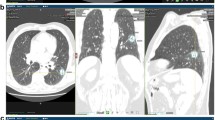

Hounsfield unit attenuation and iodine concentration were both significantly higher in metastatic (Attenuation: − 80.1 ± 192.0 HU; IC: 1.6 ± 0.5 mg/ml) than in benign lung nodules (Attenuation: − 170.5 ± 173.5 HU; IC: 1.4 ± 0.5 mg/ml; both p≤0.05). However, for both parameters, a significant data overlap was observed between the two lesion types (Fig. 3). Consequently, area under the ROC analysis revealed a low AUC of 0.67 and 0.58 for HU and IC, respectively, regarding benign and metastatic nodule differentiation. Pertaining to texture features, kurtosis, skewness and uniformity derived from CI showed significant differences between benign nodules and lung metastases, while for iodine map derived features, significant differences were found for entropy, kurtosis, uniformity and UPP; Table 2 shows the comparison of mean values of all tested features between benign and metastatic lung nodules. Figure 4 depicts exemplary cases of metastatic and benign lung nodules with entropy feature maps, which was the most powerful iodine map-derived feature.

Examples of benign nodules as shown in conventional images (CI; left column), iodine maps (IM; second column from the left) and entropy texture maps derived from CI and IM (right columns). It is revealed that some benign and metastatic nodules may be clearly distinguished by means of their iodine uptake (top row vs bottom row) while some benign nodules show comparable iodine concentration values as metastases (second vs third row), hampering accurate differentiation